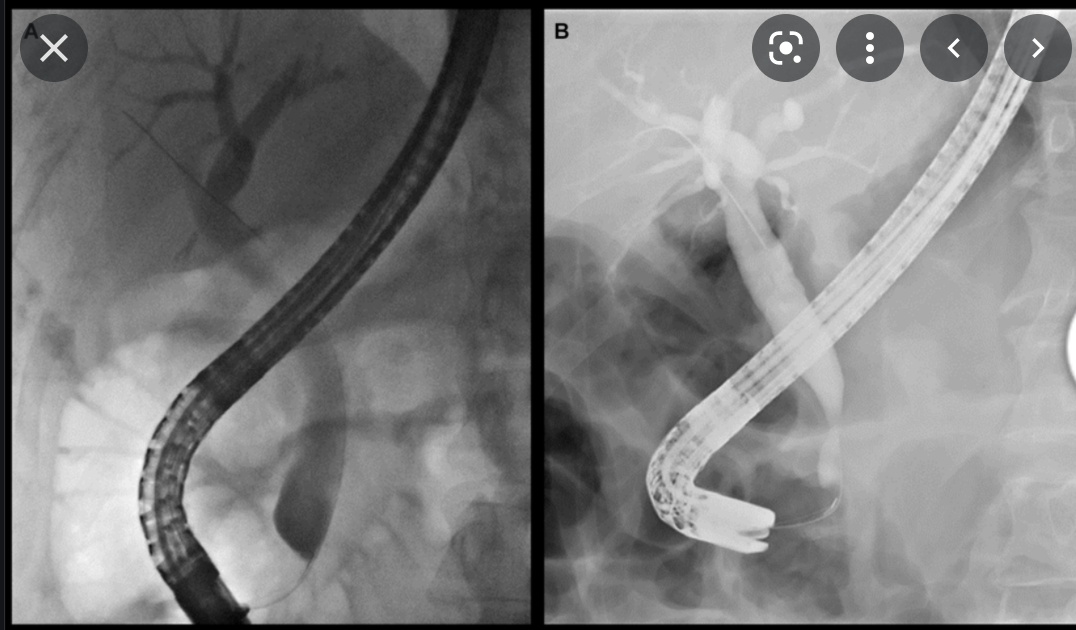

What is MRCP

- Fat sat T2 imagines of the upper abdo

- bile is hyper intense

- images of the biliary and pancreatic ducts can be rendered by maximum signal intensity projection recons (MIPS)

- Common indications

- unsuccessful ERCP

- ERCP contraindicated

- biliary-enteric anastomoses

- chledochojejunostomy

- billroth II

How common are biliary cancers?

ERCP/MRCP finding:

Smooth, thick wall, can have a short or long stricture

ERCP/MRCP finding:

Smoothly narrowed biliary duct, even with stricture

RFs: 2

benign stricture

Risk factors:

recurrent cholangitis

surgical intervention